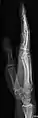

- Hand - DP and Oblique

Left hand by dorsoplantar projection

Lateral projection

Oblique projection